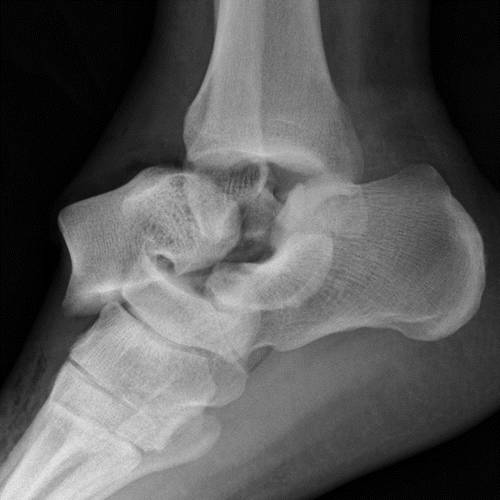

这种损伤必须与三角骨 - 一个附件后骨小梁区分开来。 在放射照相术中,后过程的断裂显示不规则的边缘(图13),而三角骨是圆形或椭圆形,具有光滑的皮质边缘(图14)。 双侧X线照片的价值有限,因为据报道三分之二的病例是双侧的(32)。 如果射线照片不确定,应进行CT。

图13b后突骨折。 (a)右足的外侧X光片显示在距骨后方的小骨质碎片(箭头)。 (b)右脚的轴向CT图像显示后路过程骨折(箭头)以及粉碎的程度和程度。